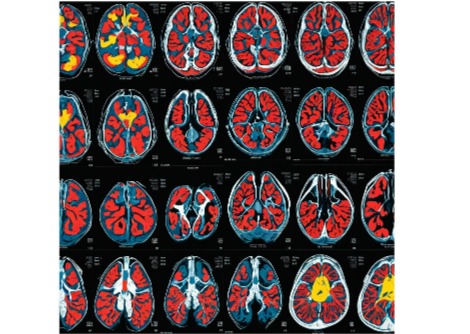

هل يؤثر هيكل دماغك على خطر الإصابة بالاكتئاب ؟

رسم خريطة لشبكة الوضع الافتراضي في الدماغ البشري: دراسة تشريحية تشير إلى أن لها تأثيرًا واسع النطاق